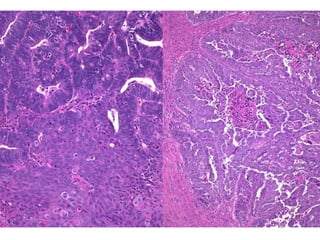

Hiperplasia complexa com atipias / Neoplasia intraepitelial endometrial (EIN)

EINAtrofia

EIN (hematoxilina-eosina) PTEN (imunoistoquímica)

Phosphatase and tensin homolog (PTEN)

Adenocarcinoma endometrioide

do endométrio